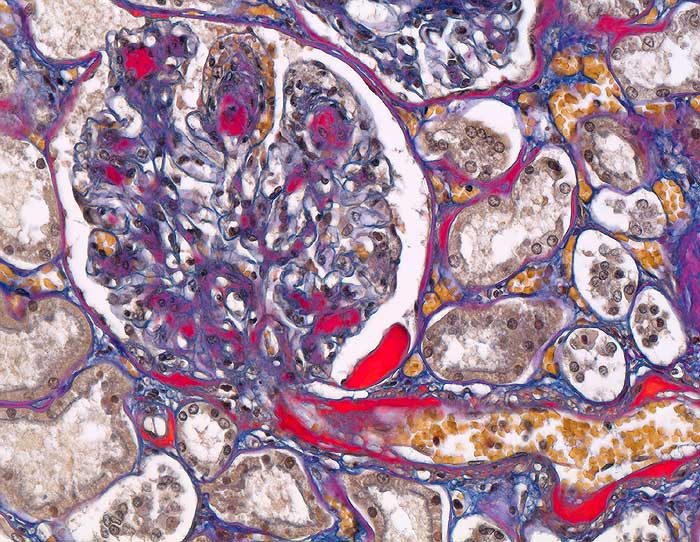

• Verbreiterung des Mesangiums mit Ausbildung von Knoten(noduläre Glomerulosklerose).

• Exsudative Läsionen: Hyaline Schlingenkappen (Proteinthromben in Glomerulumschlingen, im virtuellen Präparat nicht sichtbar) und Kapseltropfen (Proteinablagerungen im Bowman’schen Kapselraum).

• Arteriolosklerose von Vas afferens und efferens (Gefässwandhyalinose durch Ablagerung von Plasmaproteinen und Lipiden in der Gefässwand).

• Intrarenale Atherosklerose.

• Verdickte Basalmembranen der peritubulären Kapillaren.